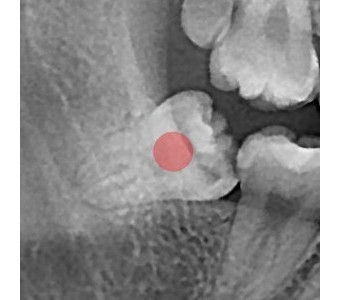

以成果证明实力。

国际摩牙齿科

真实临床案例